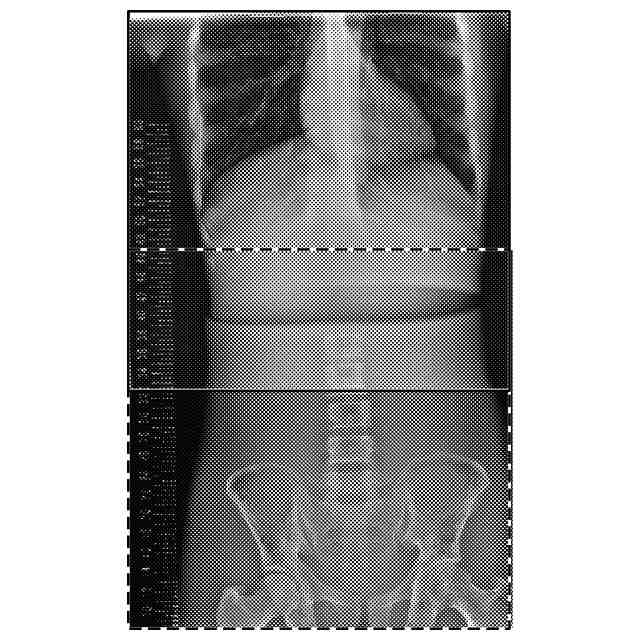

【解決手段】放射線画像処理装置として機能するコンソール30は、被写体に対し、それぞれ異なる撮影条件で撮影した複数の放射線画像を取得する画像取得部として機能する制御部31と、複数の放射線画像のうち少なくとも一の放射線画像の画素値を補正する画素値補正部、複数の放射線画像を合成して一の合成画像を取得する画像合成部として機能する画像処理部36と、を備え、複数の放射線画像の各々の放射線画像は、少なくとも一つ以上の他の放射線画像との画像重複領域を有し、画素値補正部は、少なくとも一の放射線画像の画素値の最大値が、画像の階調の最大値以下となるように画素値を補正する。

従来、放射線源の照射方向を体軸方向に変えることで得た複数の画像を合成させた合成画像を作成する方法(いわゆる首振り長尺)が知られている。

当該方法においては、放射線を複数回被写体に曝射する必要がある。そのため、被写体に健康上の悪影響が生じるおそれがある。そこで、例えば特許文献1及び2には、画像撮影の度に撮影条件を変更することで曝射の影響を抑えて、画像合成時に各画像の画素値を自動で補正する方法が記載されている。

しかしながら、特許文献1及び2には、画素値補正の具体的な方法については記載されていない。そのため、合成画像の画素値が階調の最大値以上となって(いわゆる濃度飽和)黒潰れを起こし、読影が困難になり得る。